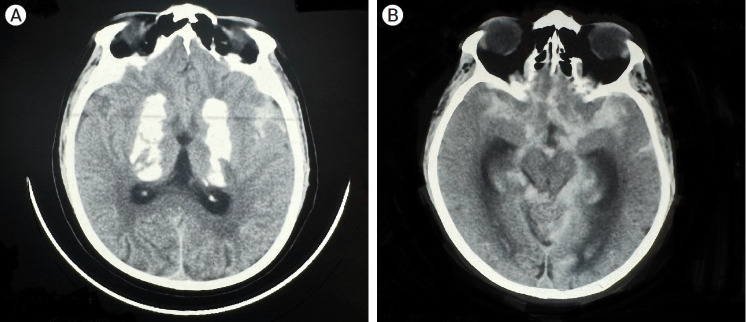

Fahr病是一种罕见的疾病,其特征是认知、精神和运动功能逐渐下降,与基底节区特发性钙化有关,通常以常染色体显性方式遗传。急性表现通常为癫痫发作;然而,我们提出了一个病例的急性表现,其中恶化的原因是动脉瘤性蛛网膜下腔出血。Fahr病与颅内动脉瘤之间的关联极为罕见,迄今为止文献记载的病例只有5例。本报告是第六次这样的案例。此外,所有先前报道的动脉瘤都局限于前循环;因此,这是第一例以后循环动脉瘤为表现的Fahr病。本病例以严重头痛主诉送急诊。头部CT显示双侧基底节区钙化及蛛网膜下腔出血。数字减影血管造影(DSA)显示颅底尖端动脉瘤。动脉瘤采用Neqstent辅助盘绕术治疗。术中动脉瘤出血发生在置入第一圈后。肝素被逆转,血压下降,动脉瘤被进一步的线圈包裹,直到出血停止。采用脑室外引流术治疗蛛网膜下腔出血和脑室内出血。Fahr病的确切机制尚不完全清楚,但据信它在由血管中的矿物质沉积引起的动脉瘤的发展中起作用。对于出现不明原因的反复发作的意识丧失的患者,即使他们已经诊断为Fahr病,也应进行脑计算机断层血管造影(CTA)以排除动脉瘤,以防止将这些发作错误地归因于癫痫。此外,对于伴有Fahr病或血管炎的动脉瘤,术前应进行血管壁磁共振成像(MRI)检查,以改善治疗计划。

Fahr's disease is an uncommon condition characterized by a gradual decline in cognitive, psychiatric, and motor functions, linked to idiopathic calcification in the basal ganglia, typically inherited in an autosomal dominant fashion. Acute presentation is most often as a seizure disorder; however, we present a case of an acute presentation in which the cause of the deterioration was an aneurysmal subarachnoid haemorrhage. The association between Fahr's disease and intracranial aneurysms is exceedingly rare, with only five cases documented in the literature to date. This report represents the sixth such case. Furthermore, all previously reported aneurysms were confined to the anterior circulation; thus, this is the first documented instance of Fahr's disease presenting with an aneurysm in the posterior circulation. The case here presented to the emergency service with the complaint of severe headache. Computed tomography (CT) of the head showed bilateral basal ganglia calcification and subarachnoid haemorrhage. Digital subtraction angiography (DSA) revealed a basilar tip aneurysm. The aneurysm was treated with Neqstent assisted coiling via jailing technique. Intraoperative aneurysmal haemorrhage occurred just after inserting the first coil. Heparin was reversed, blood pressure decreased and aneurysm was packed with further coils till the bleeding stopped. External ventricular drainage was performed to address subarachnoid hemorrhage (SAH) and intraventricular hemorrhage. The exact mechanisms underlying Fahr's disease are not fully understood, but it is believed to play a role in the development of aneurysms due to mineral deposits in blood vessels. For patients experiencing unexplained recurrent episodes of loss of consciousness, brain computed tomography angiography (CTA) should be performed to rule out an aneurysm, even if they have a known diagnosis of Fahr's disease, to prevent misattributing these episodes to epilepsy. Additionally, vessel wall magnetic resonance imaging (MRI) should be conducted preoperatively in cases of aneurysms linked to Fahr's disease or vasculitis to improve management planning.